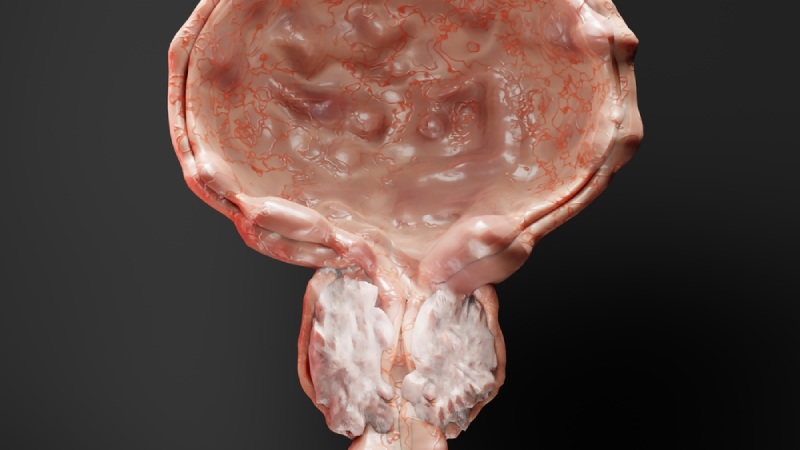

Vôi hóa tuyến tiền liệt là tình trạng lắng đọng canxi tại tuyến tiền liệt, thường gặp ở nam giới trên 50 tuổi. Tình trạng này thường không có biểu hiện triệu chứng và chỉ được tình cờ phát hiện qua hình ảnh siêu âm hoặc chụp X-quang.

Vôi tuyến tiền liệt là gì? Vôi tuyến tiền liệt, thường được chia thành hai loại chính:

Nguyên nhân vôi hóa tuyến tiền liệt hiện chưa được biết rõ. Tuy vậy vôi hóa tiền liệt tuyến thường xuất hiện ở người cao tuổi, có tiền sử mắc các bệnh về tuyến tiền liệt.

Các nguyên nhân gây vôi hóa tuyến tiền liệt được biết đến phổ biến gồm: